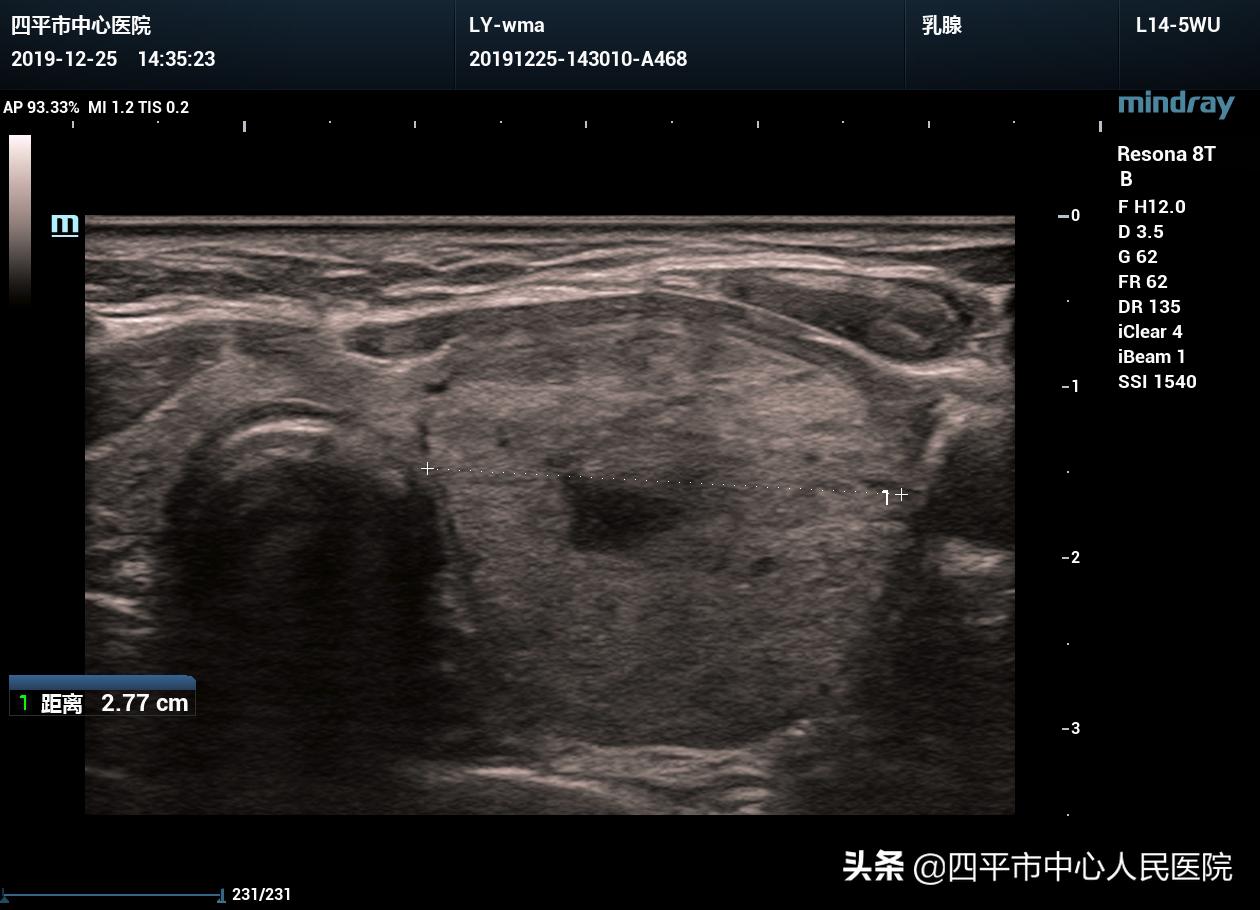

常规超声所见:甲状腺左叶见大小约4.0×2.6×2.8cm囊实混合性结节,以实性回声为主,边界清晰,形态规则,纵横比<1,CDFI:实性回声内及结节周边见血流信号。

超声提示:甲状腺左叶囊实混合性结节,TI-RADS 3级。